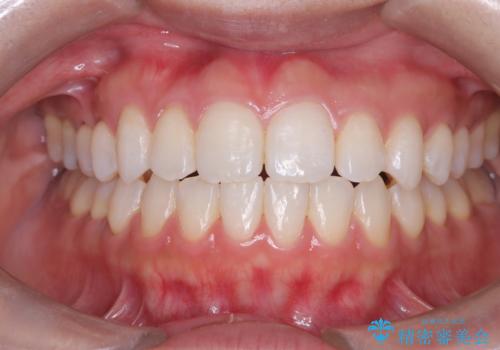

その結果、約10ヵ月という比較的短期間で歯列と咬み合わせが整い、機能面・審美面ともに良好な結果を得ることができました。

- 歯の捻じれやデコボコを主訴にご来院された患者様です。

矯正治療の精密検査を行った結果、非抜歯(歯を抜かない)矯正治療を選択いたしました。